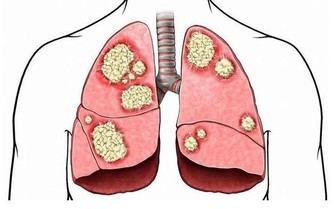

4、愛吃甜食

甜食吃多了,皺紋也會增多。過多的糖,會導致身體各部位衰老加速。

高糖飲食不僅會使腰圍增加,而且會增加糖尿病危險,破壞保持皮膚彈性的蛋白纖維,導致痤瘡和皺紋等皮膚問題。

最好選擇低糖黑巧克力,或者選擇不會導致血糖升高的自然甜味劑。